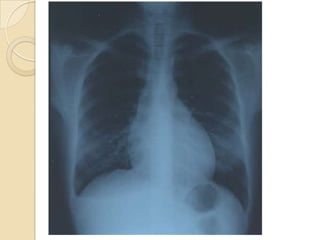

Mesotelioma (mesothelioma) pleural

maligno en una niña de once años, que

se manifestó por un derrame pleural

masivo

Radiografía de tórax (AP) que muestra

un extenso derrame pleural izquierdo

con desplazamiento mediastínico